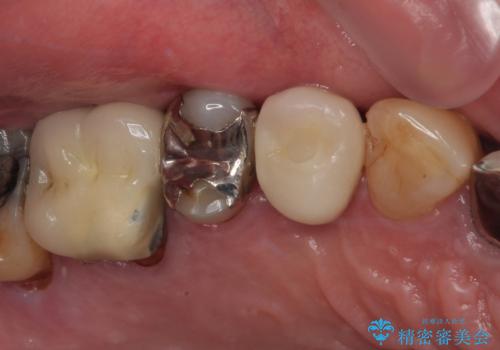

奥歯が取れた フルジルコニアクラウン

担当医 小澤俊哉